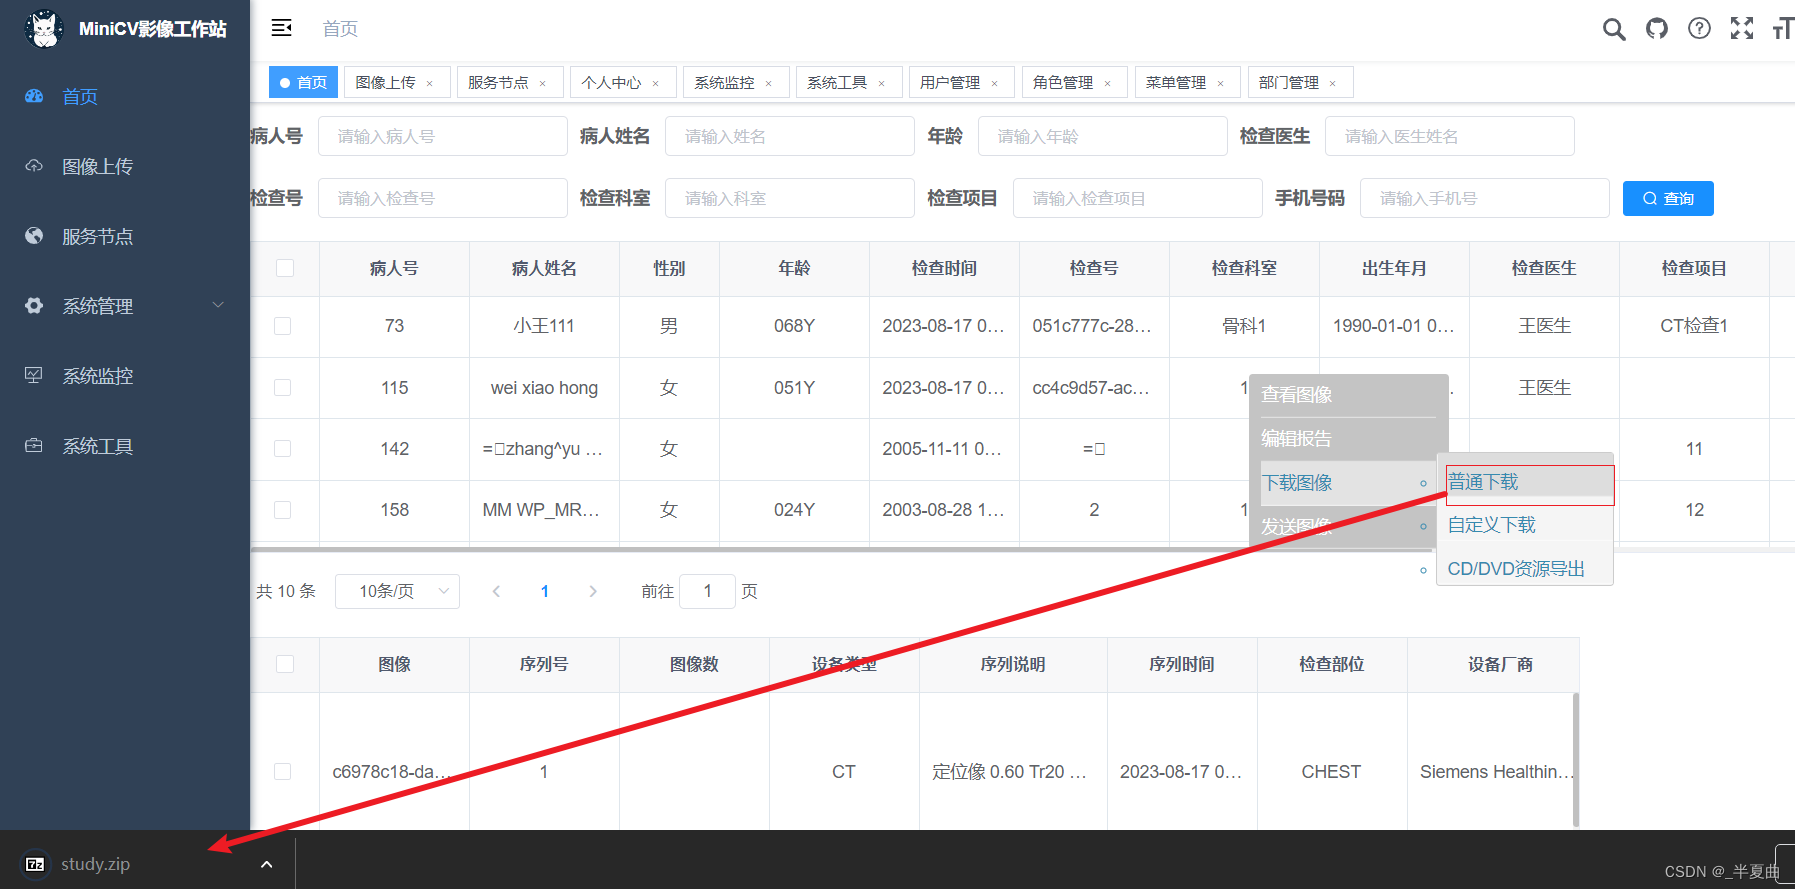

患者检查列表展示及维护功能;

检查下序列影像的列表(单帧影像预览)功能;

下载患者检查影像文件: